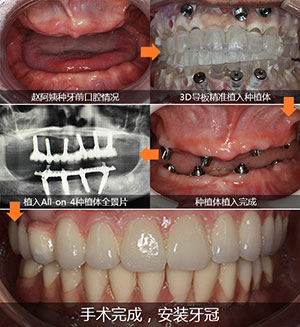

缺牙患者:赵阿姨

缺牙情况:全口牙缺失十多年,牙槽骨骨量差

主诊医生:赵海涛院长

治疗方法:All-on-4全口种植牙技术

赵海涛院长从检查初,到最后手术,全程使用数字化导航导板种植系统,术前精准模拟种植的每个过程,打印3D导板,按照导板预先的轨迹植入种植体,戴临时牙冠,手术持续了两个半小时,术后赵阿姨就能啃苹果了。